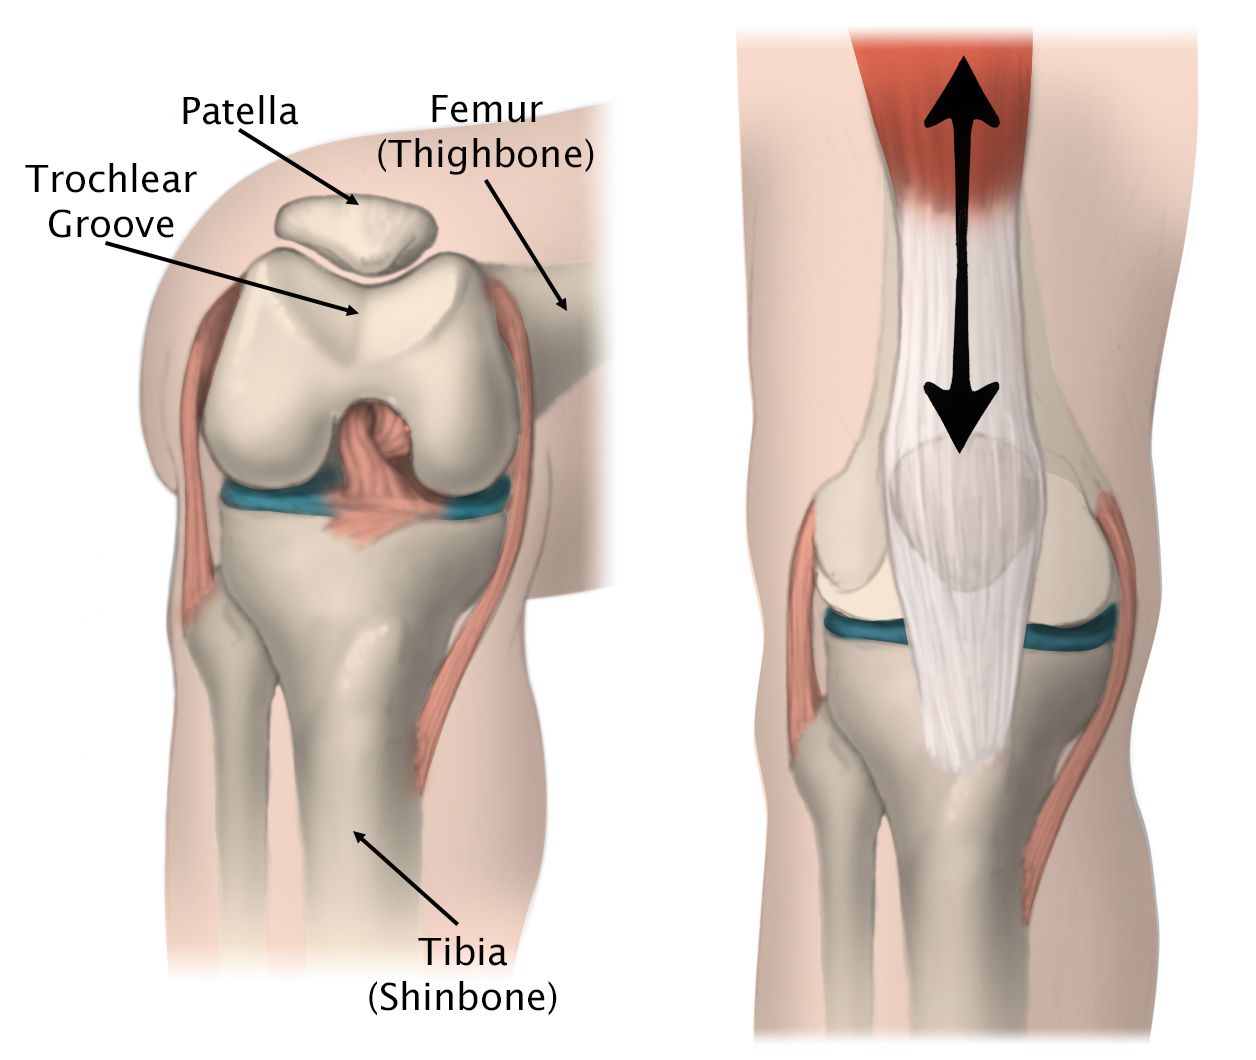

Within the patellofemoral compartment, the patella lies in a groove on the top of the femur called the trochlea. When you bend or straighten your knee, the patella moves back and forth inside this trochlear groove.

Illustration of the movement of the patella in the trochlear groove

(Left) The patella rests in a small groove at the end of the femur called the trochlear groove.

(Right) As you bend and straighten your knee, the patella slides up and down within the groove.

Reproduced and adapted from The Body Almanac. American Academy of Orthopaedic Surgeons, 2003.